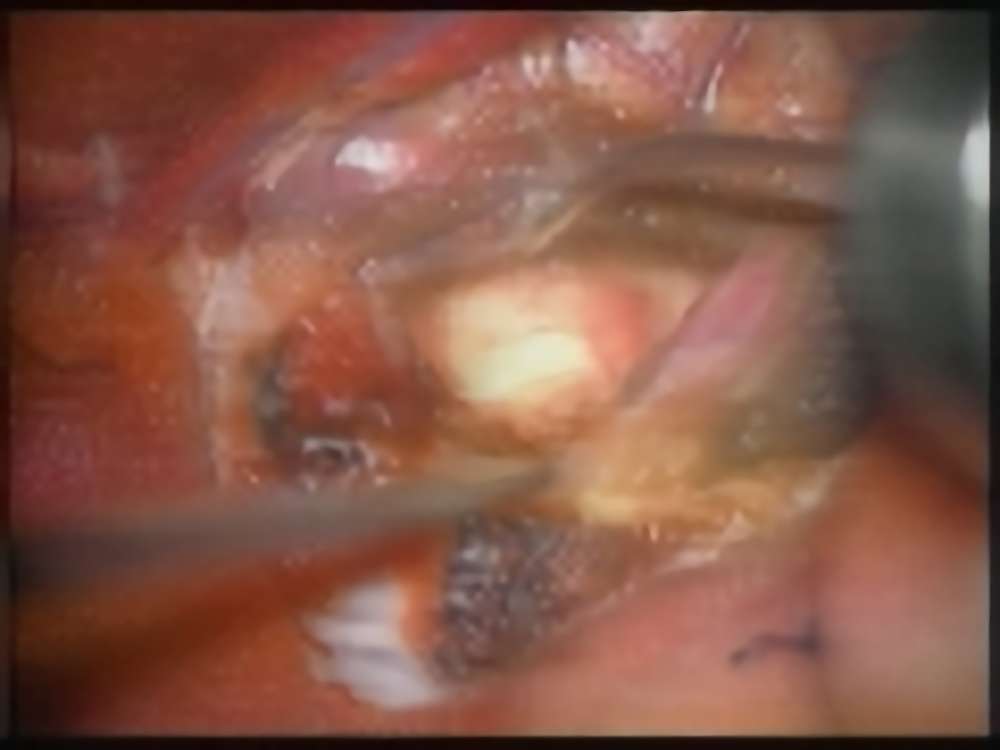

術中写真

摘出 後